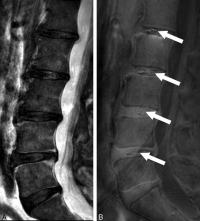

這次研究共有108名華南地區人士(平均年齡52歲,男女各半)參與。傳統的T2W MRI用作評估椎間盤退化和其他影像病徵,T1-rho MRI用作量度構成椎間盤的主要成份 “蛋白聚醣”水平。UDS 病徵被定義為在UTE MRI上檢測到的超高或超低光束帶。參與者的基本資料、病歷、腰背痛情況及活動能力指標(ODI Oswestry Disability Index)亦於研究時採納為臨床指標之一。

研究結果發現39.8%的參與者有UDS病徵,而其中61.4%的UDS是發生於下腰部位置。有UDS病徵比沒有UDS病徵的參與者有更多機會患有椎間盤退化、椎間盤突出、脊椎移位及椎體變異(Modic Change)。有UDS病徵的椎間盤的蛋白聚醣含量比沒有UDS的椎間盤低。而逾六成UDS病徵是無法在傳統的T2W MRI上檢測到。有UDS病徵的參與者比沒有的參與者有更嚴重的腰背痛,而同時其活動能力亦較差,而傳統的T2W MRI並無法找出此關連。研究更指出約四成患者於多節腰椎皆出現UDS病徵,其患上嚴重腰背痛的機率比單節腰椎出現UDS的患者更高。